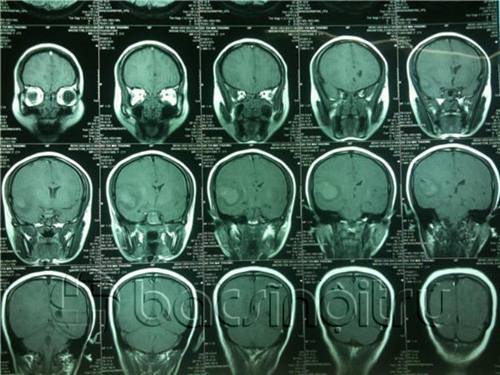

Vì bệnh nhân có thai, chúng tôi đã cân nhắc chọc dịch não tủy trước và cho kết quả: Dịch não tủy hồng đều cả 3 ống xét nghệm và để không đông (sau 6 giờ). Sau đó để có chẩn đoán chính xác và an toàn cho thai nhi, y bác sĩ khoa cấp cứu đã quyết định chụp MRI sọ não và mạch não kết luận: Hình ảnh khối dạng máu tụ thùy thái dương phải. Sau khi làm việc với gia đình sản phụ, báo cáo tình hình, chúng tôi tiến hành ca mổ”.